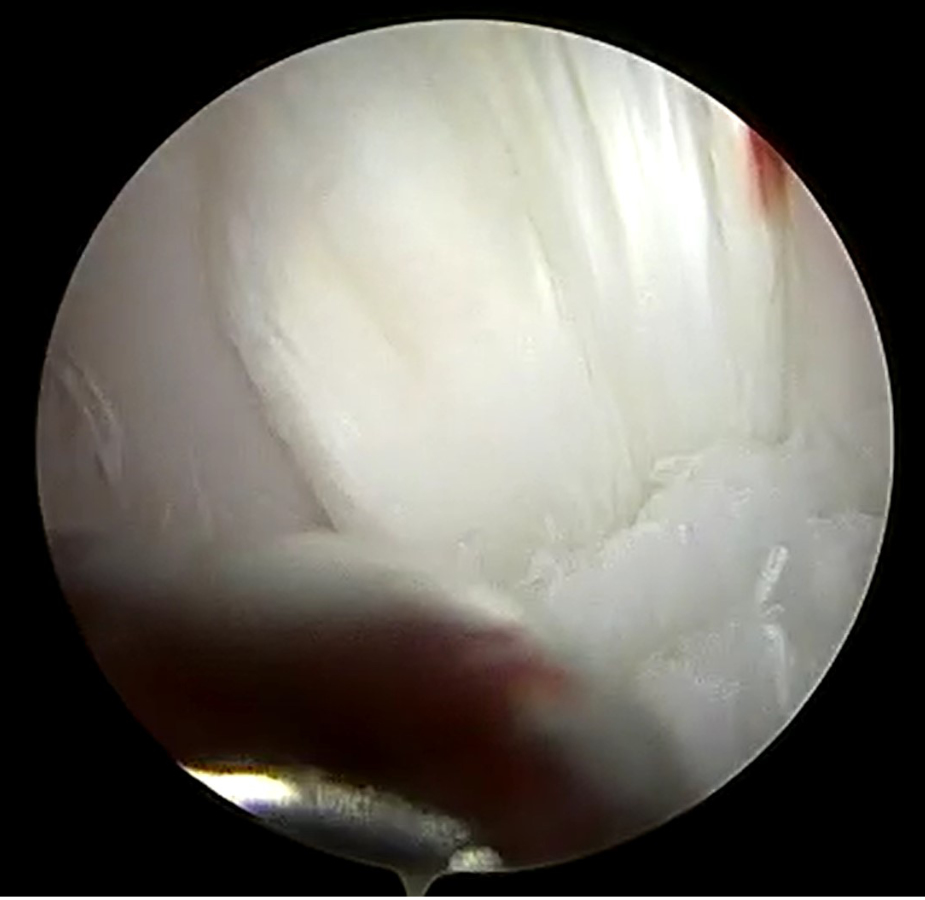

A fine needle aspirate and cytology of the left forelimb mass were performed and were consistent with a lipoma. A routine complete blood count and chemistry panel were performed and were unremarkable. Radiographs were performed of the left stifle (Figure 1), which revealed moderate to significant intracapsular soft tissue opacity (consistent with joint effusion), very mild osteophytosis at the proximal aspect of the femoral trochlear ridges and the insertion site of the cranial cruciate ligament (CCL) on the tibial plateau, as well as moderate cranial tibial subluxation. No other concerning changes were noted.

Figure 1